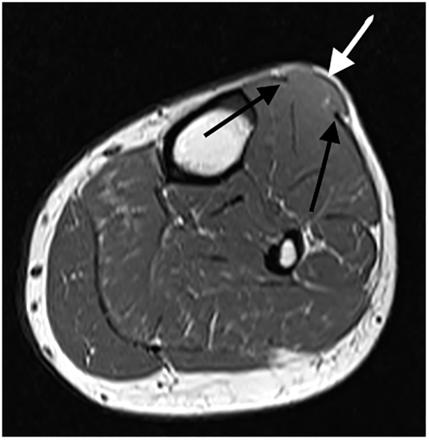

超声误入歧途的肌肉肌疝

图片尺寸900x650